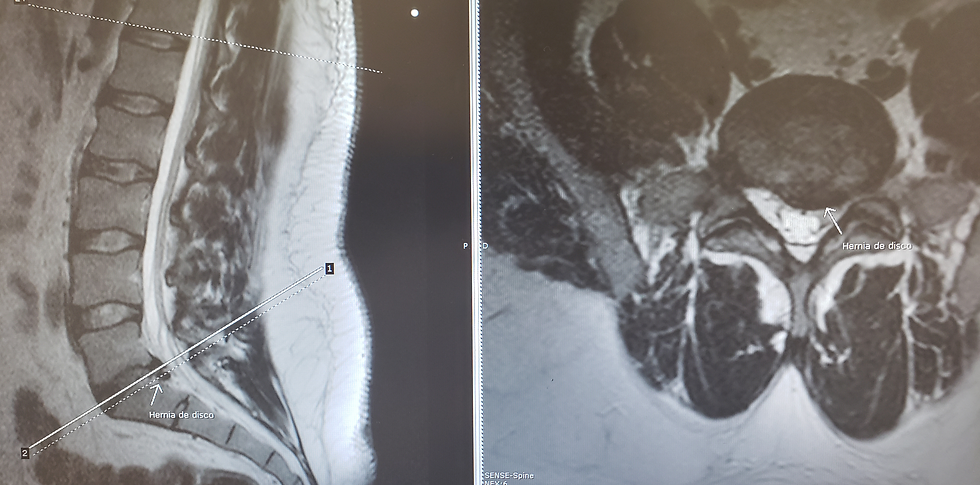

La resonancia magnética es el estudio de oro para la patología discal. Permite evaluar la calidad del disco y la presencia o no de hernias discales.